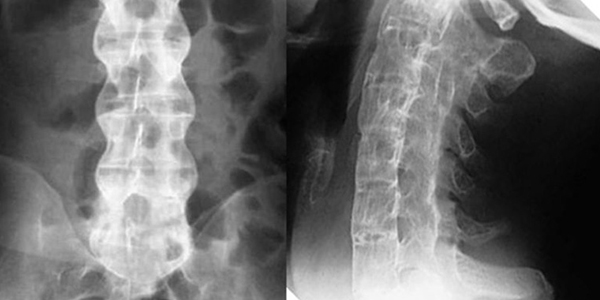

- Chụp X-quang tư thế thẳng và nghiêng để phát hiện các đốt sống bị hẹp, hẹp lỗ liên hợp đốt sống, gai xương sống.